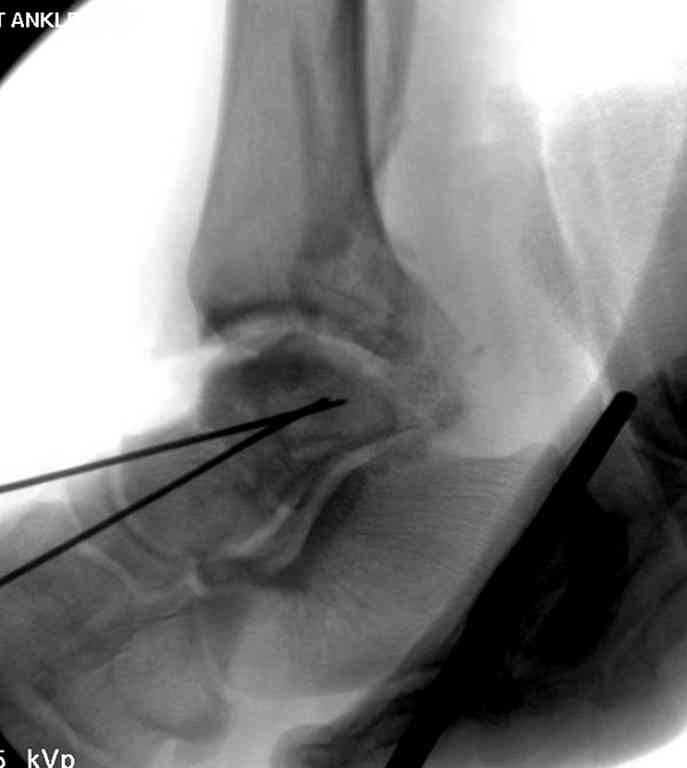

Прошу коллег помочь советом.3 дня назад поступила пациентка 23 года с переломом шейки ладьевидной справа, переломом лодыжек и заднего края б/берцовой кости со смещением и подвывихом кзади, переломом внутреннего мыщелка правого бедра без смещения. Дежурными хирургами проведена репозиция в левом г/ст суставе успешная, попытка репозиции таранной кости ухудшило положение отломков. Планируем провести повторную репозицию и фиксацию винтами. 1. Закрытая репозиция рентгенконтоль интраоперационный (аппарат Арман) ификсация из заднее-наружного доступа. 2. При неудачной закрытой репозиции переходим на открытое вправление двумя доступами медиальным и латеральным "по ходу оси таранной кости" и через дополнительный задний доступ вводим винты кортикальные 4,5 мм или 3,5 мм 3. после открытой репозиции фиксация двумя винтами через боковые доступы погружая их под суставную поверхность Сергей Зырянов ЦРБ Новосибирская область

Здесь на фото примеры:

Переломовывих тарана с повреждением медиальной стороны. Через 4 часа после поступления проведена репозиция и фиксация тарана после Irrigation&Debridment. Частичное несращение медиальной лодыжки не беспокоит, вернулся к активному образу жизни. Полная нагрузка разрешена через 11 недель. Финальные снимки через 11 месяцев.

Второй случай прооперирован вчера.

10 дней назад поступил с открытым повреждением медиальной лодыжки и переломо вывихом таранной кости. Ургентно сделана репозиция с наложением наружного фиксатора + Irrigation&Debridment.

Во время репозиции выявили повреждение заднего сухожилия м. тибиалис и задней большеберцовой артерии. Медиальную рану удалось закрыть частично и установлен вакуум.

Дважды провели Irrigation&Debridment с заменой вакуума.

Вчера провели фиксацию.

Из-за многооскольчатости дистальной части малоберцовой, где невозможно было провести фиксацию шурупами, перелом зафиксирован подпирающей пластиной, которая должна служить дополнением отсутствующей дистальной части малоберцовой (lateral cortex substitute).

Для стабильности два шурупа на синдесмоз.

Медиальную рану с приближенными краями продолжаем вакуумировать (KCI). Наружный фиксатор оставлен на пару недель, надеюсь, небольшая рана будет гранулировать и закроется без кожной пластики. Фиксация медиальной ложыжки не планируется.